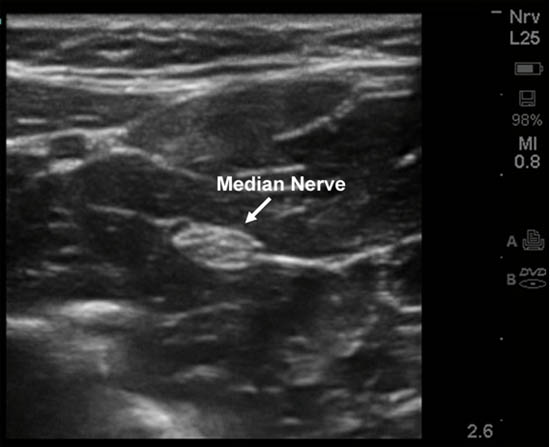

Ultrasound-guided blockade of the median nerve can be performed at various points along its course between the elbow and wrist but it is best accomplished at the mid distal forearm.[3] In this location, it is easier to avoid the brachial artery as well as tendons, which can appear similar to nerves under ultrasound. In the mid distal forearm the nerve is visible between the flexor digitorum superficialis and the flexor digitorum profundus. Another ultrasound technique is to locate the ulnar nerve and artery under the flexor digitorum superficialis at the level of the mid forearm and then trace the muscle layer laterally until the median nerve is located. It is also possible to block both the median and ulnar nerve at this location (Figure 2).[1-3]

Figure 2. Ultrasound-guided median nerve blockade in the forearm